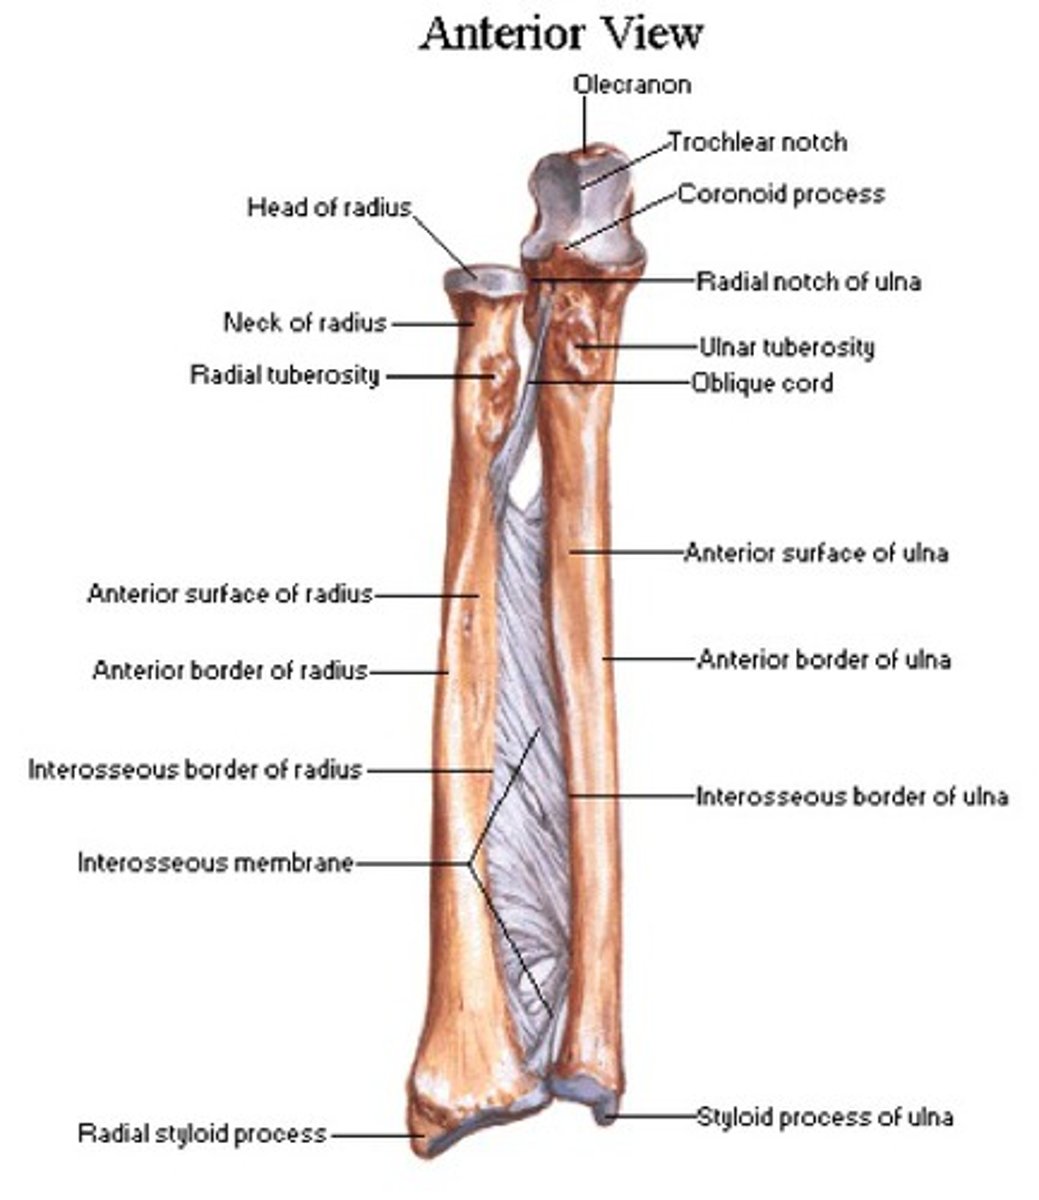

Bones of the forearm:

radius and ulna

The ulna is the ___________ bone of the forearm

Stabilizing bone

Location of the ulna:

Medial and longer of the two forearm bones

Ulna articulation:

- Proximal end (more bulky) with humerus & head of radius

- does not form wrist distally

Features of the ulna:

- olecranon

- coronoid process

- ulnar tuberosity

- radial notch

- shaft

- head of ulna

- ulnar styloid process

Olecranon of the ulna:

Superior, most proximal portion.

What does the olecranon of the ulna articulate with?

Articulate with olecranon fossa of the humerus on its

anterior side

What is the function of the olecranon of the ulna?

Serve as a short lever for extension of the elbow

Coronoid process of ulna:

Inferior to the olecranon process

What does the coronoid process of the ulna articulate with?

Articulate with coronoid fossa of humerus on its anterior side

Ulnar tuberosity of the ulna:

Attachment for the brachialis muscle

Radial notch of the ulna:

Inferolateral to the coronoid process, receives the head of the radius

Shaft of the ulna:

Gets thinner distally

Head of the ulna:

Enlargement on distal part of the shaft

Ulnar styloid process:

Distal ending of the head of the ulna

What is the radius capable of doing?

Can pivot on the ulna (supination and pronation) due to their parallel position

Location of the radius:

Lateral & shorter of the forearm

What does the radius articulate with?

- Articulate with the ulna (proximally and distally)

- articulate with carpal bones on the distal side of radius

What structure of the upper extremities does the radius form?

Forms the wrist joint

What does the radius control in the forearm?

Controls supination and pronation

Head of the radius:

Articulates with the capitulum of humerus and with the radial notch of the ulna

Neck of the radius:

Inferior to the head

Shaft of the radius:

Gets thicker distally opposite to the ulna

Ulnar notch of the radius:

Articulates with the head of the ulna

Radial styloid process of radius:

Distal ending on lateral side of the shaft of the radius